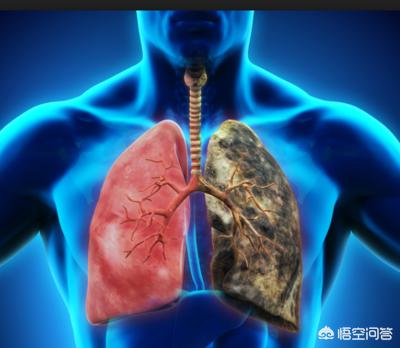

首先要明确一点,我们称做肺癌的,都是恶性肿瘤,没有良性肺癌这一说法,肺上的良性肿瘤都有其他的名字,如硬化性血管瘤、腺瘤、脂肪瘤、错构瘤等。对于良性的肿瘤,一般都是可以治疗的;而对于恶性的肺癌,早期肺癌治疗效果是不错的,晚期肺癌相对来说预后要差很多。

1、戒烟并远离吸烟人群。在我国,大约有3亿多的烟民,我国烟草一直保持着多项世界第一的记录,这也造就了我国有最多的肺癌患者。珍爱生命,远离烟草,吸烟作为目前已知的肺癌最高危的因素,对国民的身体健康造成了非常大的影响;同时,二手烟的危害同样非常的明显,尤其是对妇女和儿童。研究表明,长期和吸烟的人生活在一起的女性,其肺癌的发病率明显高于正常女性。因此,戒烟不仅有利于自己,也有利于家庭成员的身体健康。